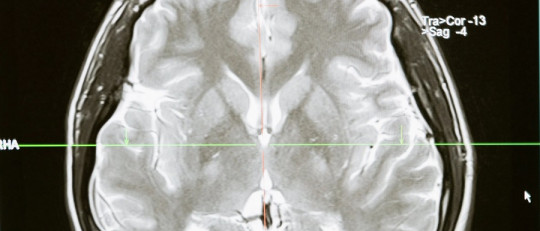

El mecanismo de acción de la tioridazina es el bloqueo de los receptores dopaminérgicos D2 postsinápticos en el sistema mesolímbico del cerebro. El bloqueo también explica los efectos extrapiramidales que se observan con la toma de tioridazina.